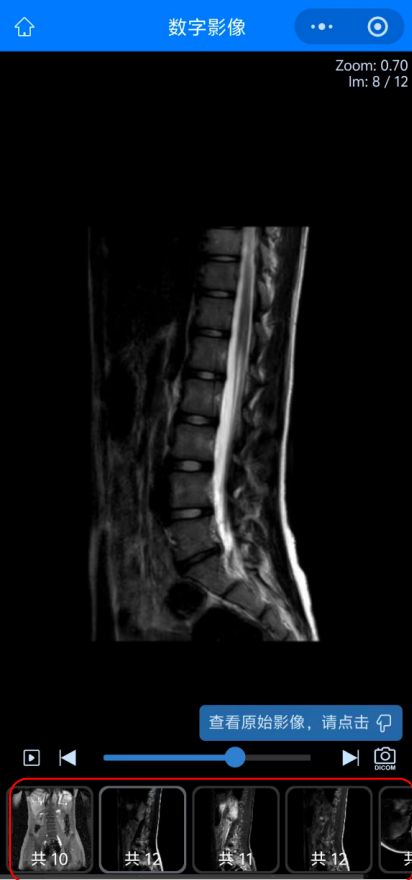

05 而點(diǎn)擊“查看影像”后查看到的患者的影像圖像,可以選擇下方紅色方框內(nèi)不同影像檢查或圖象處理方法來(lái)查看不同影像圖像。